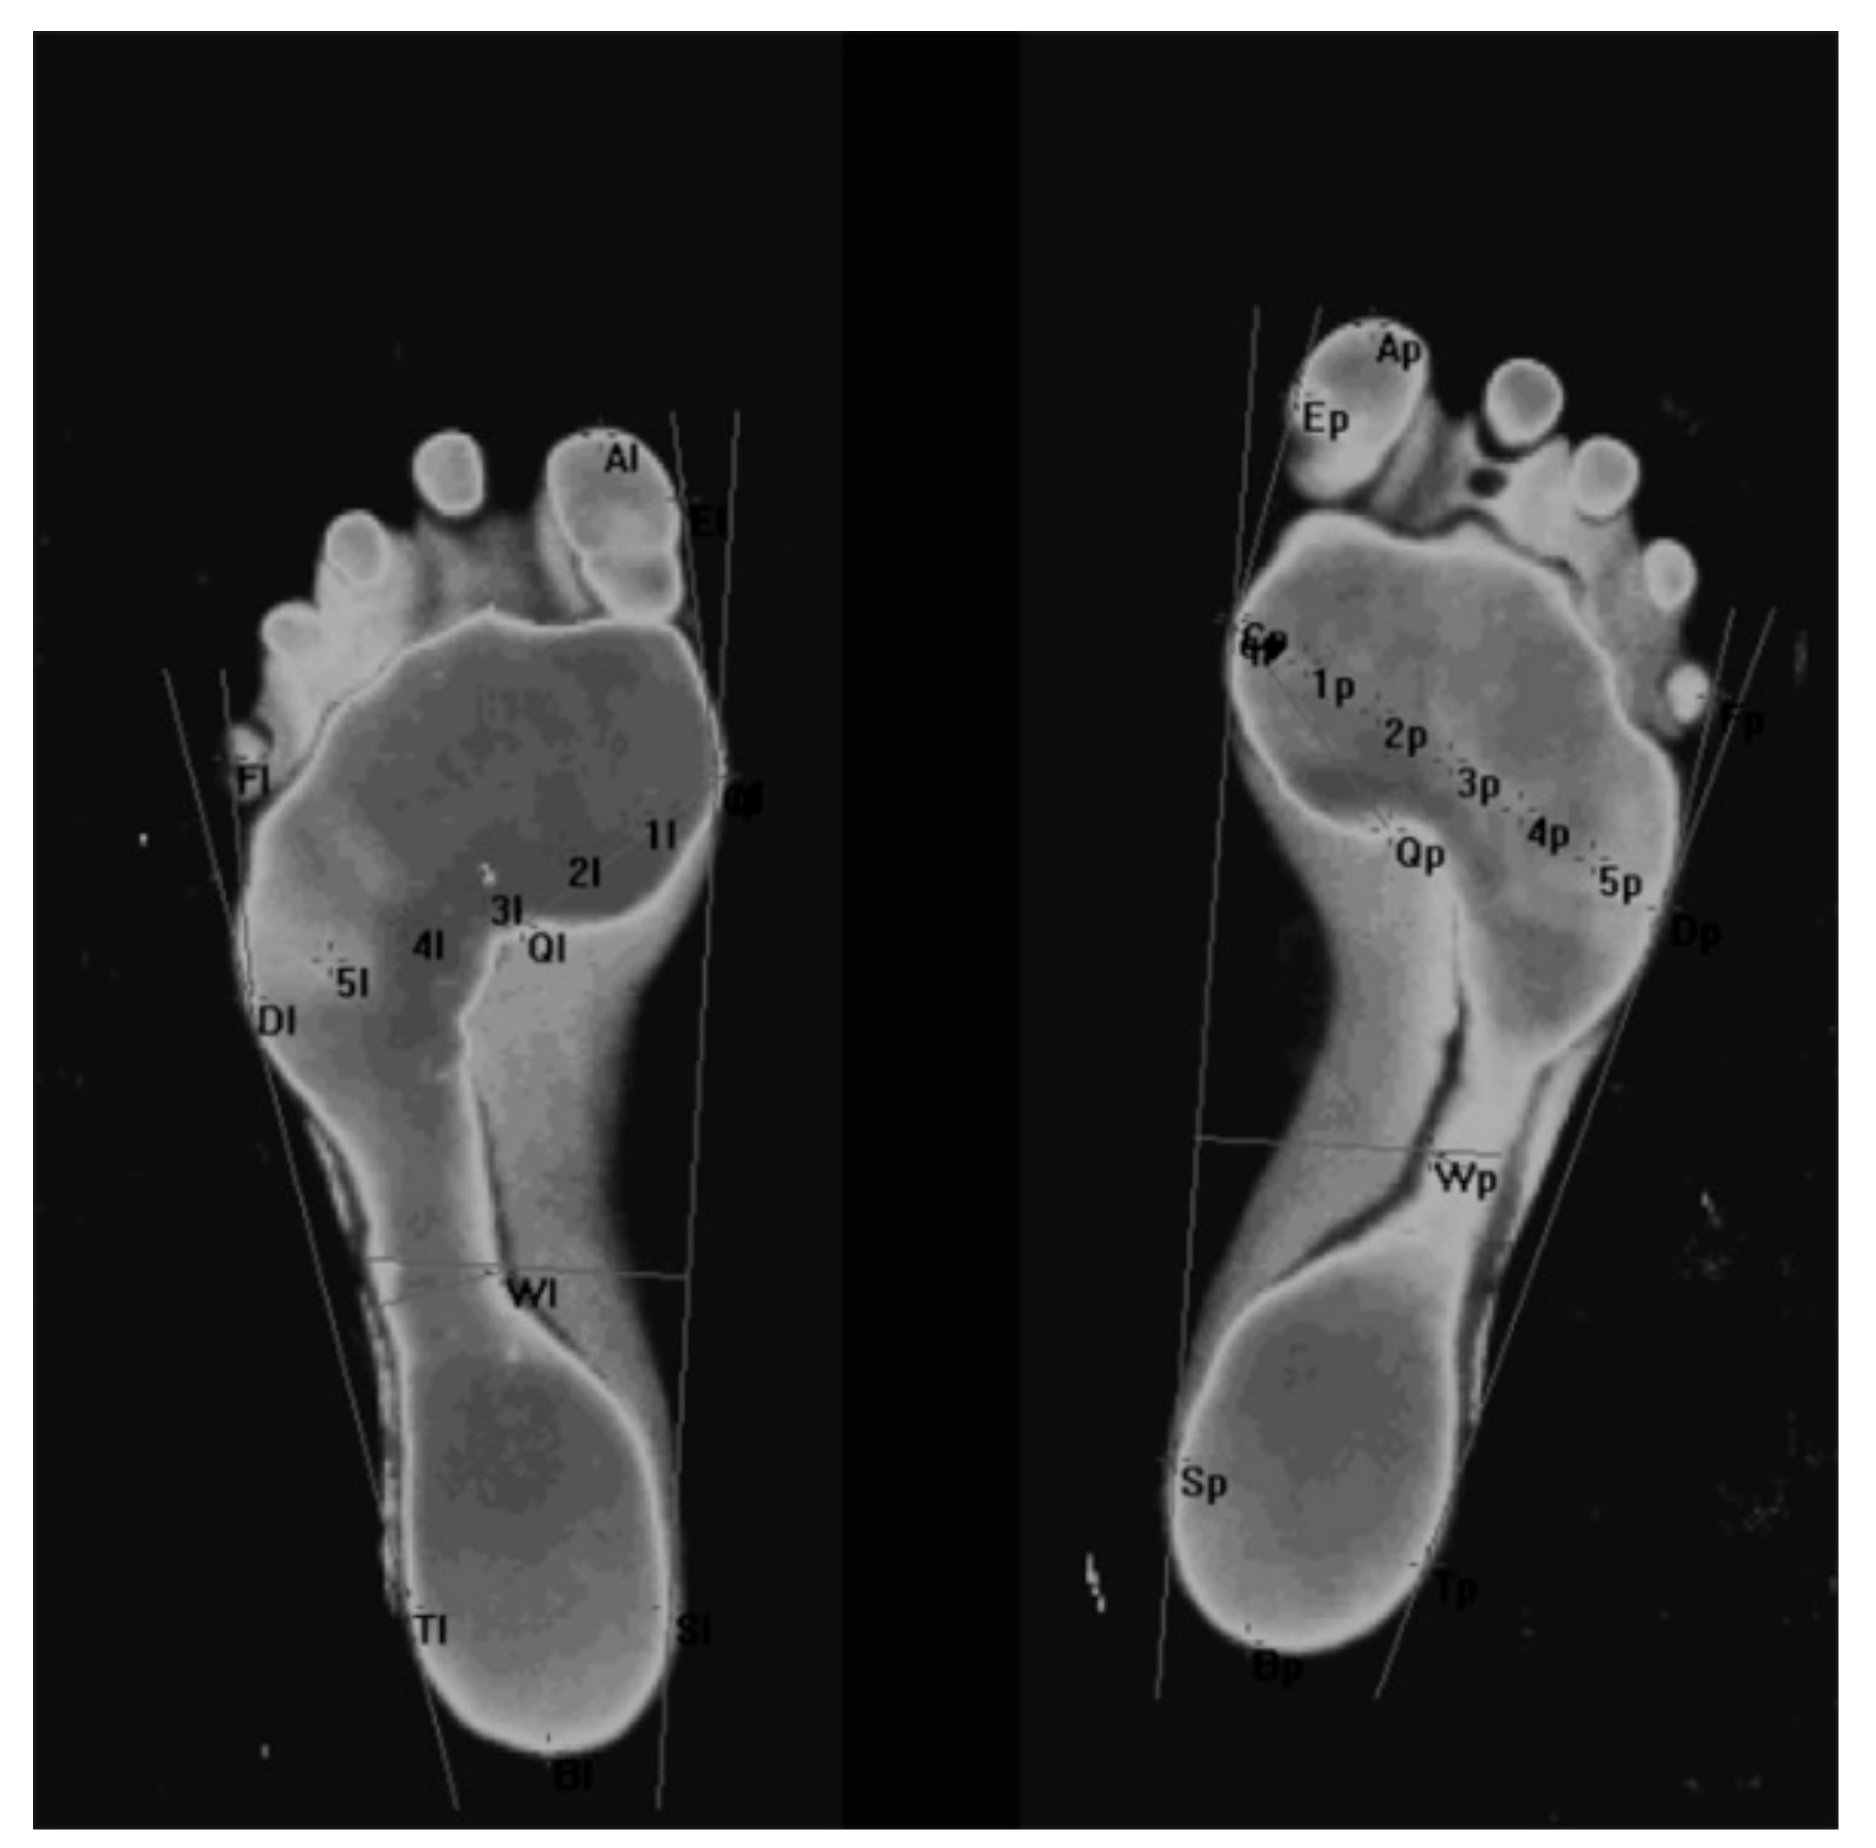

- Foot length (LG) is the line connecting the farthest points in the forefoot and the rearfoot (A–B), in mm (Figure 1).

- Foot width (WD) is the line connecting the metatarsale tibiale (C) and metatarsale fibulare (D) points, in mm (Figure 1).

- Clarke’s angle (CL) is located between the tangent to the medial edge of the foot (C-S) and the line joining the point of the largest recess (point Q) with the point of contact of the medial tangent to the forefoot (point q), in degrees. Clarke’s angle defines the medial longitudinal arch (Figure 2).

- The Wejsflog index (WI) is the ratio of the length to the width of the foot. The WI determines the transverse arch of the foot (Figure 1).

- Hallux valgus angle (ALPHA) is located between the tangent line to the medial edge of the foot (C–S) and the tangent to the pad of the big toe, derived from the metatarsale tibiale point (E–C), in degrees. The ALPHA defines the position of the big toe (Figure 1).

- The angle of the varus deformity of the fifth toe (BETA) is located between the tangent line to the lateral edge of the foot (D–T) and the tangent to the pad of the fifth toe, derived from the metatarsale fibulare point (F–D), in degrees. The BETA defines the position of the fifth toe) (Figure 1).